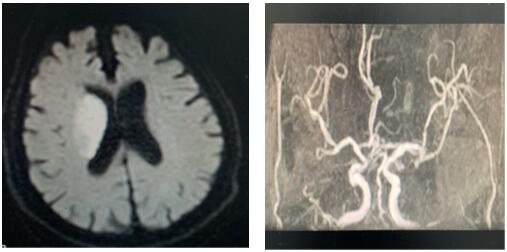

患者治療前影像圖

2020年2月11日,我院卒中中心接到急救電話,一位91歲老人,突發(fā)左側(cè)肢體無力,言語不能,卒中急診李博濤醫(yī)師迅速判斷,考慮急性腦卒中,在NICU王偉偉副主任帶領(lǐng)下,確保疫情防范安全,立即開通卒中綠色通道,卒中護(hù)理團(tuán)隊(duì)井井有條做好溶栓工作,謝小攀醫(yī)師嚴(yán)密觀察患者生命體征,溶栓效果及不良反應(yīng),治療后左側(cè)肢體肌力恢復(fù)4級,達(dá)到理想效果。為患者在疫情肆虐中緊急發(fā)病的慌亂心情中,帶來了溫暖與希望。

戰(zhàn)疫情,防卒中,我們刻不容緩!2020年2月14日,同往常一樣,卒中中心接診一名65歲患者,突發(fā)右側(cè)肢體活動不靈,卒中急診張帆醫(yī)師迅速判斷,考慮急性缺血性腦卒中,在NICU王偉偉副主任帶領(lǐng)下反復(fù)排查新型冠狀病毒感染,溶栓治療工作有條不紊,張沖醫(yī)師嚴(yán)密觀察患者生命體征,溶栓效果及不良反應(yīng),治療后右側(cè)肢體肌力恢復(fù)4級,基本生活自理,達(dá)到溶栓效果。這是我們工作的常態(tài)!無論疫情是否,我們卒中人始終堅(jiān)守一線,從進(jìn)入NICU,一直到他們帶著笑容走出大門,那一張張笑臉是我們繼續(xù)堅(jiān)持的動力!